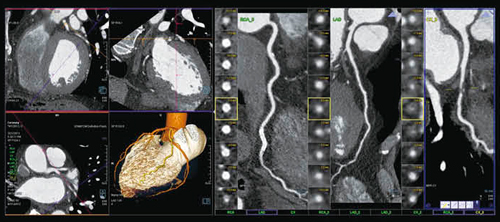

syngo.viaのCT Coronary Analysisでは,CTから画像転送が行われると,画像のスタディ名から適切なワークフローが選択され処理が行われる。心臓VR像が自動的に作成され,そこから複数の冠動脈を抽出してcurved MPR像と短軸断面像が表示される。読影医は,自動的に処理された画像から任意の冠動脈を選択して読影することが可能で,ワークフローが大きく改善する。図2は,胸痛で来院した患者の当日CT検査の画像だが,ステント内の再狭窄を疑って撮影されたCTで,新たにLCX#12に高度狭窄が認められた。

図2 syngo CT Coronary Analysis(冠動脈)